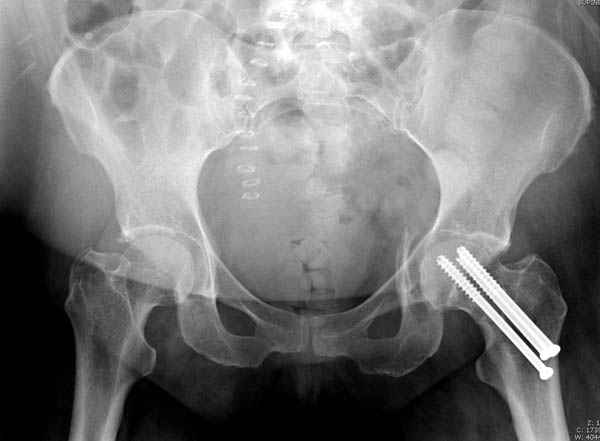

На снимке ацетабулума редко встречающийся очень низкий перелом,

наверное, трудно было репозицию через один доступ? Перелом как бы

замкнулся в квадрилатеральной поврехности.

Имя     : 1 acetabulum fem neck injury.jpg

Тип     : image/jpeg

Размер  : 23064 байтов

Долгое ожидание повышает риск АВН головки,

рекомендуется ургентная фиксация шейки в первые сутки, а в дальнейшем таз.

В данный момент скелетное вытяжение получается через перелом шейки, а

фиксированный перелом шейки будет участвовать в процессе вытяжения через

канюлированные  шурупы.